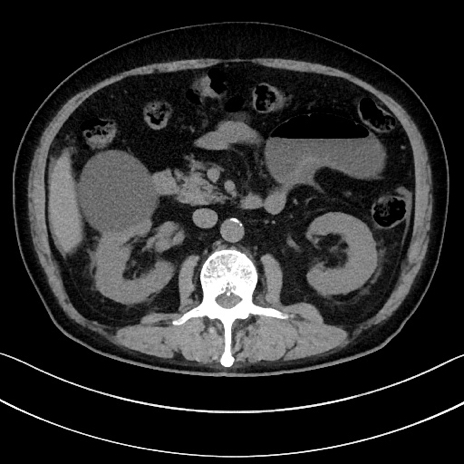

症例15(横断像)

【症例】70歳代男性

【主訴】腹痛

【現病歴】今朝から腹痛あり。全体的に痛い。特に左上の方。排ガスが今日はない。冷や汗が出る。

【既往歴】直腸癌術後

【身体所見】左側腹部〜上腹部に圧痛あり。腹膜刺激症状明らかなではない。軽度反跳痛。左下腹部に術後瘢痕あり。

【データ】WBC 7700、CRP 0.02